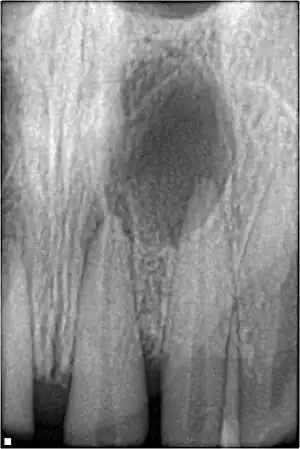

Pulpal necrosis

Pulp necrosis usually occurs either as ischaemic necrosis (infarction) caused by disruption to the blood supply at the apical foramen or as an infection-related liquefactive necrosis following dental trauma (2). Signs of pulpal necrosis include[42]

- Persistent grey colour to tooth that does not fade

- Radiographic signs of periapical inflammation

- Clinical signs of infection: tenderness, sinus, suppuration, swelling

Pulpal obliteration

4–24% of traumatized teeth will have some degrees of pulpal obliteration that is characterized by the loss of pulpal space radiographically and yellow discolouration of the clinical crown. No treatment is needed if it is asymptomatic. Treatment options will be extraction for symptomatic primary tooth. For symptomatic permanent tooth, root canal treatment is often challenging because the pulp chamber is filled with calcified material and the drop-off sensation of entering a pulp chamber will not occur.[44]